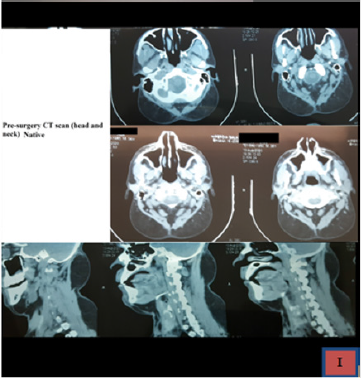

Here we report our case of a 37-year old male patient, without any relevant clinical history, which came in our hospital for this painless, bilateral and symmetric growing mass on the posterior aspect of the neck region, which grew in the last 4 years and speed up in the last year. At the beginning, the lesion was considered trivial by the patient. His main complaint was esthetical. At the physical examination, two well distinct lesions were described, as the left side was slightly bigger than the right side (10 cm; 8 cm as thier biggest diameter) and without any invasion of the skin layers. We also provided the patient with a CT scan of the head and neck regions (Figure 1), which confirmed the adipocytic origin of the tumor, as well as its lacks of infiltration of other compartments. There were no sign of airway obstruction or involvement of the superior aspect of mediastinum. The lesion was well delimitated and encapsulated.

Our case is classified as a type Ia Madelung disease, as it is shown in the pre-operative CT scans (Figure 1), with a bilateral mass over the posterior aspect of the nuchal region and the occipital bone. The other most common locations are visible in the table above. ”The pathogenesis of this disease has not been completely defined, as such the abnormal proliferation of fat tissue is not related to an increase in caloric intake, but it looks like an active proliferation of the adipose tissue. The suggested-most mechanisms are defects in the respiratory chain or mutations/deletions in mitochondrial DNA” [4,5]. ”Lipomatous fat deposits may originate from functionally defective brown adipous tissue and the tumoral fatty cells have an abnormal metabolic behaviour, which is characterized by a defect of the catecholamines acute lipolytic action. Some sort of alcoholic drinking disorder is present in more than 90%, however our case did not show any sign of chronic alcoholic intake. A decrease in the beta-adrenergic receptors and subsequent defects in mitochondrial DNA may be the explication of pathogenic alcohol action over the fat tissue” [6]. ”Even though that the history, epidemiology and clinical features are the basis of MLS diagnosis [7] in some cases may be challenging, due to the common arise of obesity in the general population (1;4). Moreover, such patients usually presents with other significant commorbidities, such as type II diabetes mellitus, glucose intolerance or hyperuricemia. Diseases associated with chronic alcoholic consumption (macrocytic anemia, hepatopathy, periferal neuropaties) are very common is MSL” [7]. Our patient did not show any sign of liver suffering or chronic alcoholic consuption associated diseases. Although alcohol withdrawal and weight loss are recommended, these measures are not effective to reverse/ stop the progression of the tumors. Currently, surgical treatment is the only option available, and so the fat masses removal remains the only therapy of choice. However the overall recurrence rate is describe as up as 63% of cases [7].